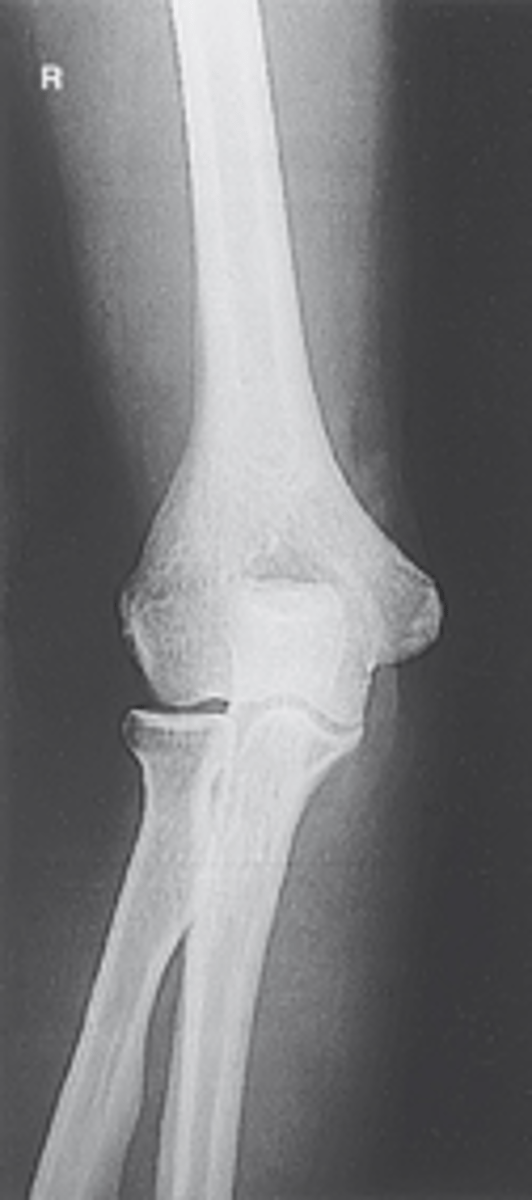

AP Elbow

AP elbow humerus parallel

AP elbow forearm parallel